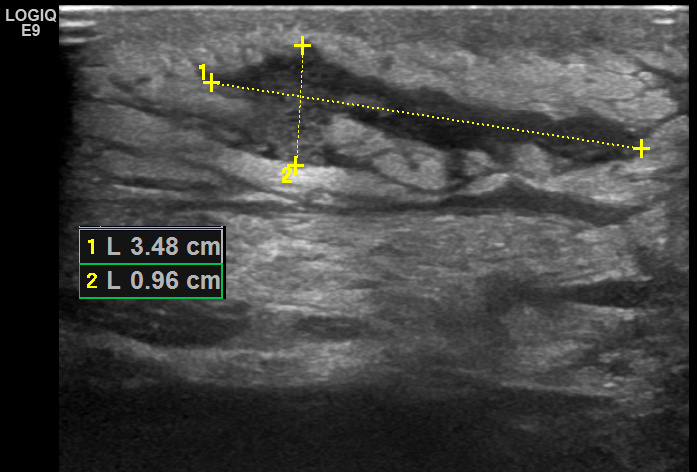

При ультразвуковом исследовании в подкожной клетчатке определяется неправильной формы полость размерами 35х10 мм, с нечеткими неровными контурами и неоднородным жидкостным содержимым, с наличием большого количества мелкодисперсной эхогенной взвеси, смещающейся при дозированной компрессии датчиком.

Рис. 01. Подкожный абсцесс.

В окружающей жировой ткани отмечается повышенная "дольчатость" с наличием гипоэхогенных прослоек между дольками, что указывает на выраженный отек подкожной клетчатки.